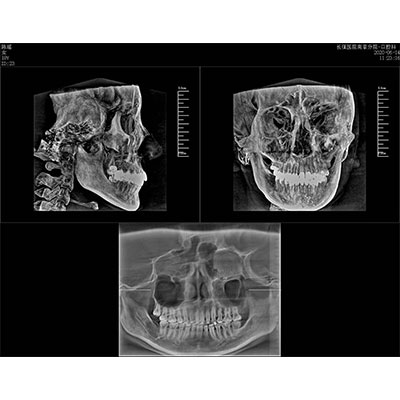

专有三维重建算法,可提供任意位置高清断层影像。

可同时观察轴向面、冠状面和矢状面图像,方便临床诊断。